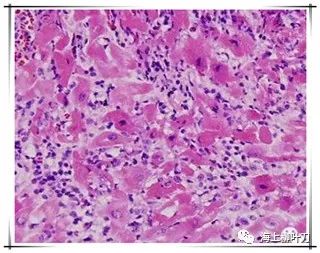

7.100倍還不是看得很清楚,放大400倍就很明顯了,一個(gè)個(gè)藍(lán)點(diǎn)就是淋巴球。這是很厲害的猛暴性心肌炎,整個(gè)心臟都被淋巴球浸潤(rùn)了。